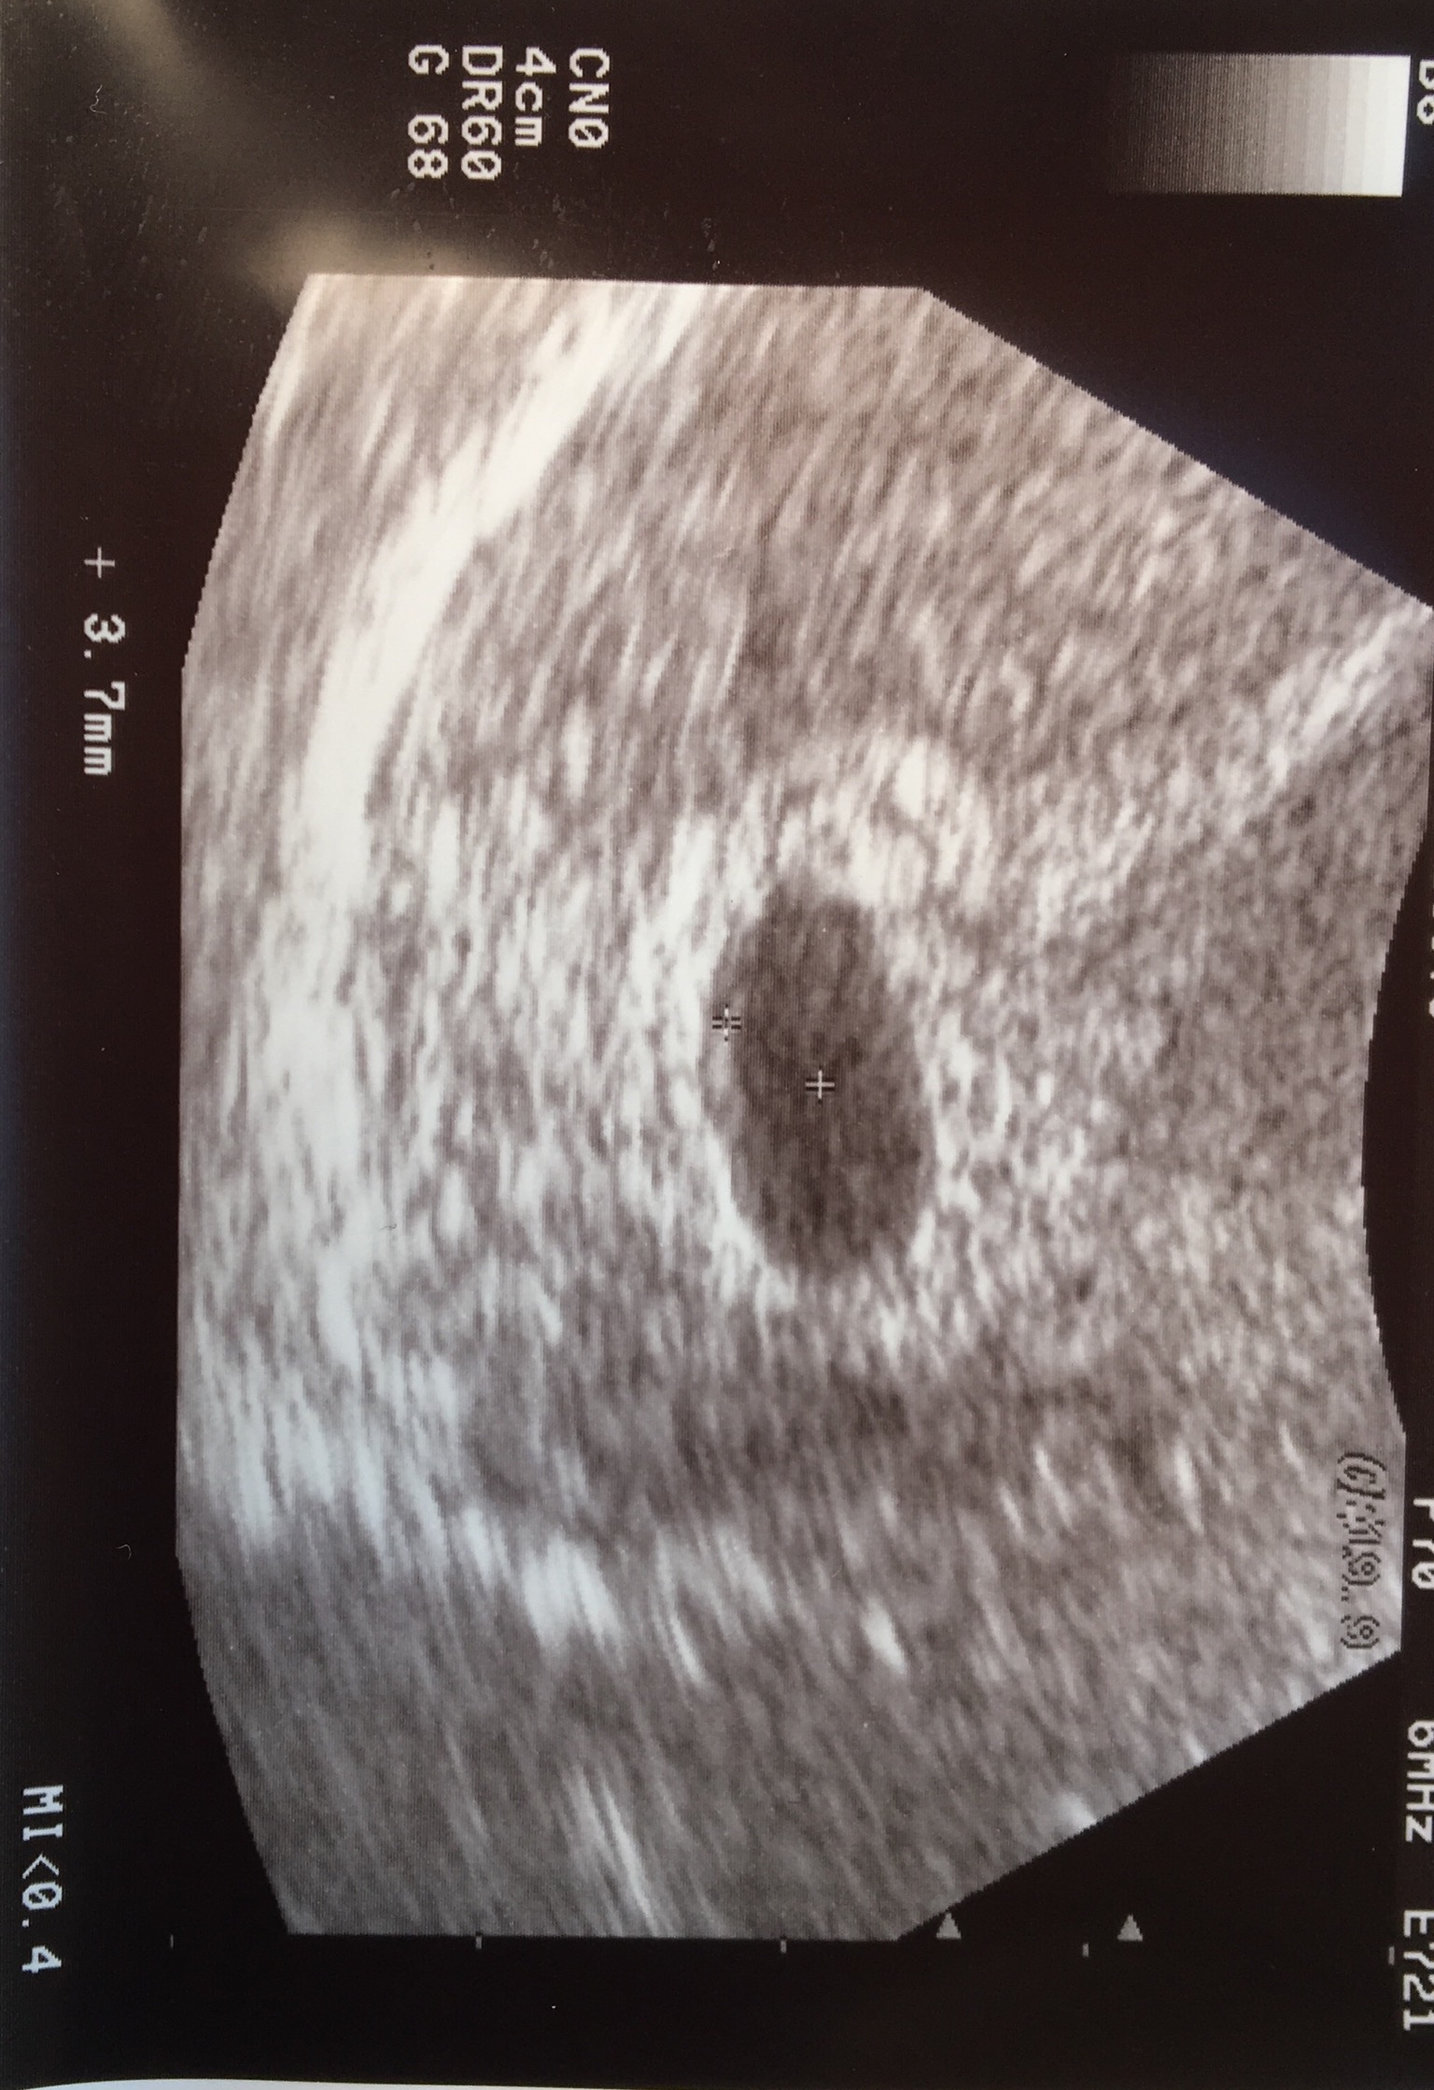

7 weeks 5 days two tiny babies and two tiny heartbeats 😍😍